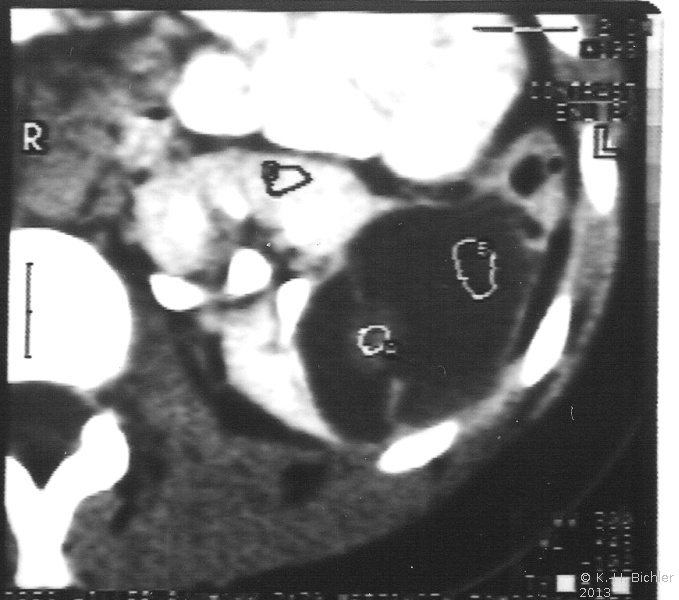

Die Computertomographie zur Bestimmung der Tumorausdehnung, zum Ausschluss einer zystischen Nierenfehlbildung (Differentialdiagnose) und zur Suche nach einem eventuellen kontralateralen Nierentumorbefall von Interesse. Außerdem dient das CT zur Flankierung der Chemotherapie (Ergebniskontrolle) (Abbildung 7,8,9).

(Die Abbildungen 7-8 wurden uns freundlicherweise von Herrn Dr. med. Günter Antes, Kempten überlassen)